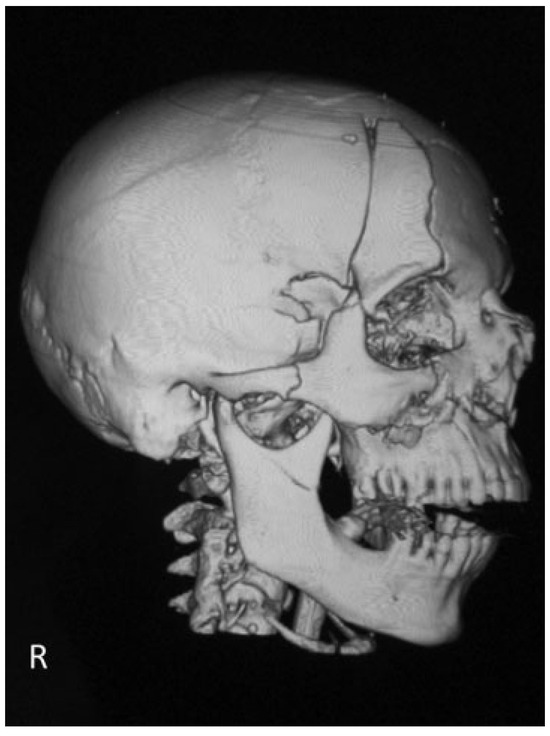

Natural Course of Orbital Roof Fractures

by Liselotte H. M. Stam, Eppo B. Wolvius, Warren Schubert and Maarten J. Koudstaal

Craniomaxillofac. Trauma Reconstr. 2014, 7(4), 294-297; https://doi.org/10.1055/s-0034-1378188 - 3 Jun 2014

The natural course of several isolated and nonisolated orbital roof fractures is reported, by showing four cases in which a “wait and see” policy was followed. All four cases showed spontaneous repositioning and stabilizing of the fracture within less than a year. This [...] Read more.

The natural course of several isolated and nonisolated orbital roof fractures is reported, by showing four cases in which a “wait and see” policy was followed. All four cases showed spontaneous repositioning and stabilizing of the fracture within less than a year. This might be explained by the equilibrium between the intraorbital and intracranial pressures. Full article